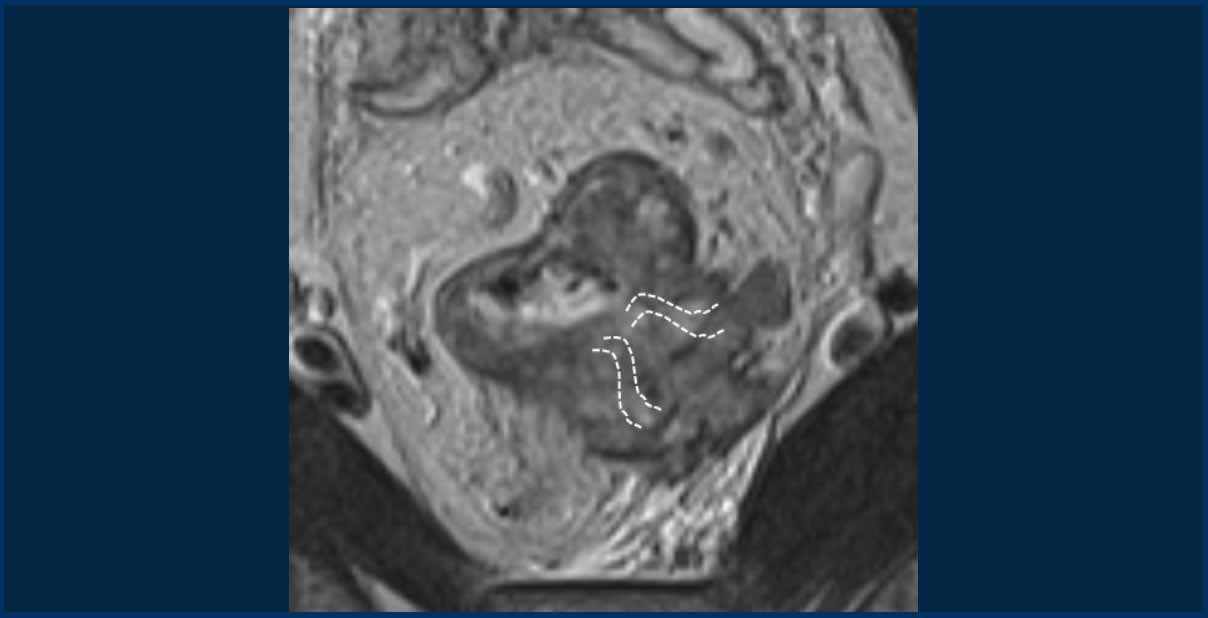

Pitfall: Assessing EMVI in tumors with massive extramural growth

In large T3cd-4 tumors with extensive extramural extension into the perirectal fat, a practical approach is to classify these as EMVI+.

In the example shown, the tumor extends into the perirectal fat from 3 to 5 o’clock, obliterating the mesorectal fat in this region.

While individual vessel involvement may not be discernible, it is reasonable to assume that vessels in this area are completely invaded by the tumor.

The dashed lines indicate the potential location of vessels.